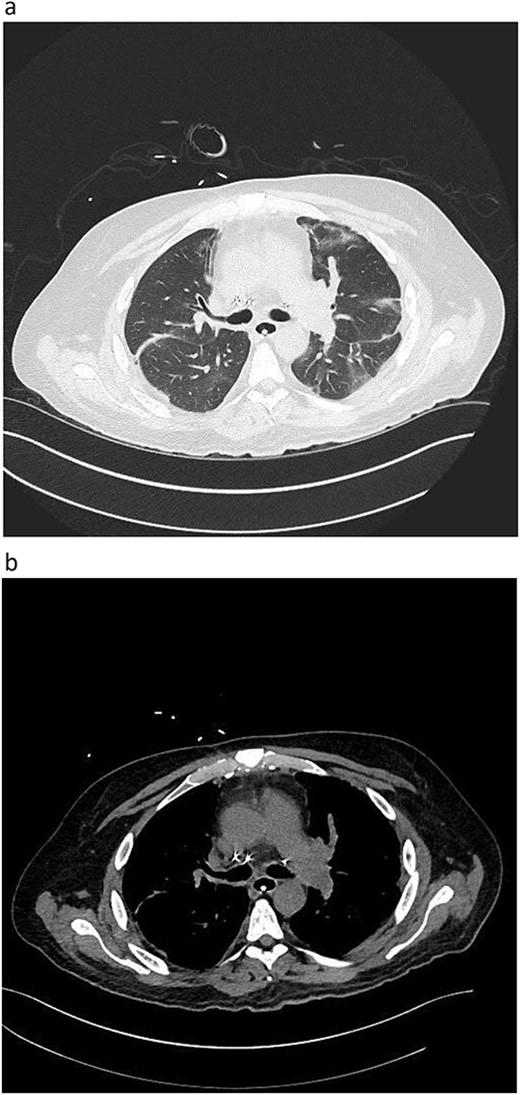

Postoperative graft CT scan: recipients had bilateral lung reduction due to over size.